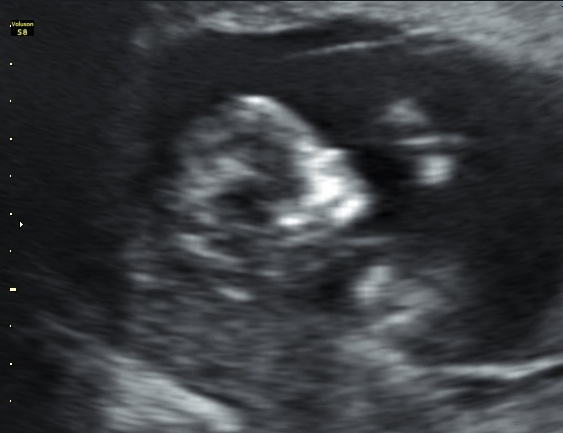

Hi,just wondering what's the best shot, girl or boy?

Can't see the nub, outside of the shot.

Based on skull theory i would say boy